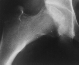

Avascular necrosis may not present for up to two years after the initial injury. That is what happened to this girl. This hip will have a severe permanent disability form this avascular necrosis.